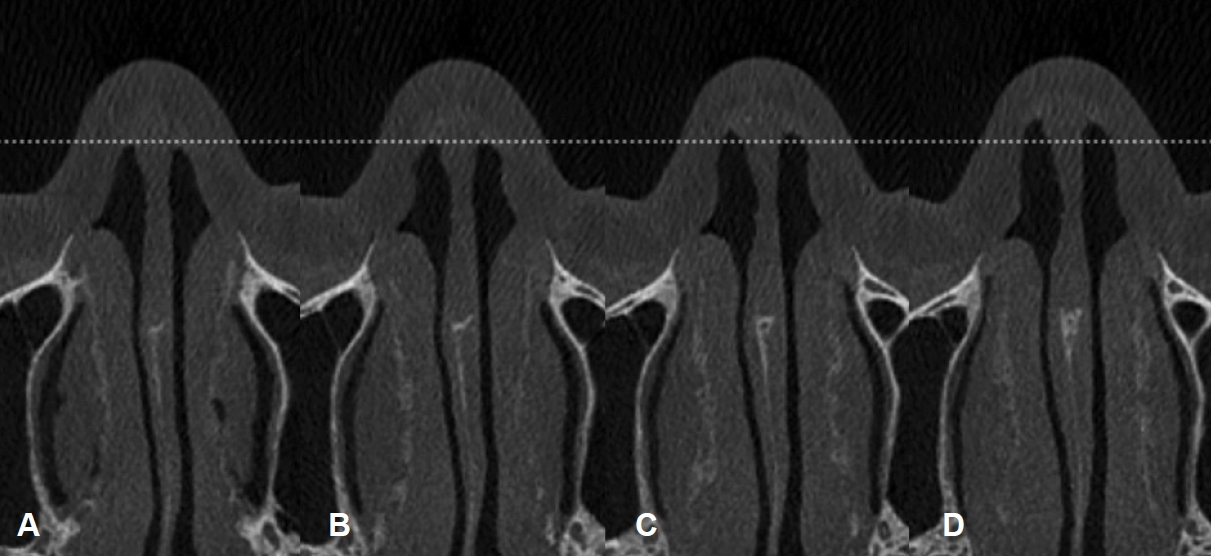

정확한 비밸브 협착을 정의하는 것도 합의가 필요한 사항이다. 과거 상외측비연골과 비중격이 이루는 각도를 측정하 여비밸브 협착을 정의한 연구들이 있었지만, 위에 설명한 것과 같이 비밸브에서 두 구조물이 이루는 각도가 명확히 측정할 수 있는 예각이 아니기 때문에 적용이 어렵다. 결국은 양측의 비밸브의 모양과 넓이를 비교해서 판단하는 방법이 현실적인 분류라고 생각된다[6]. 본 연구자는 Fig. 4A와 같이 양측 비밸브의 모양과 넓이가 거의 동일하면 정상, Fig. 4B와 같이 한쪽 비밸브가 반대쪽에 비해 확연하게 좁지만, 공간이 관찰되면 부분 협착, Fig. 4C와 같이 한쪽 비밸브 공간이 관찰되지 않으면 완전 협착이라는 분류를 제안한다. 부분 협착의 구체적인 정의는 좁은 쪽 비밸브에서 가장 넓은 부분에 수평선을 긋고 좁은 쪽과 넓은 쪽의 비강 폭을 측정하여, 1:3 혹은 더 큰 차이가 나지만 좁은 쪽 비밸브에 공간이 관찰되는 경우이다(Fig. 4D).